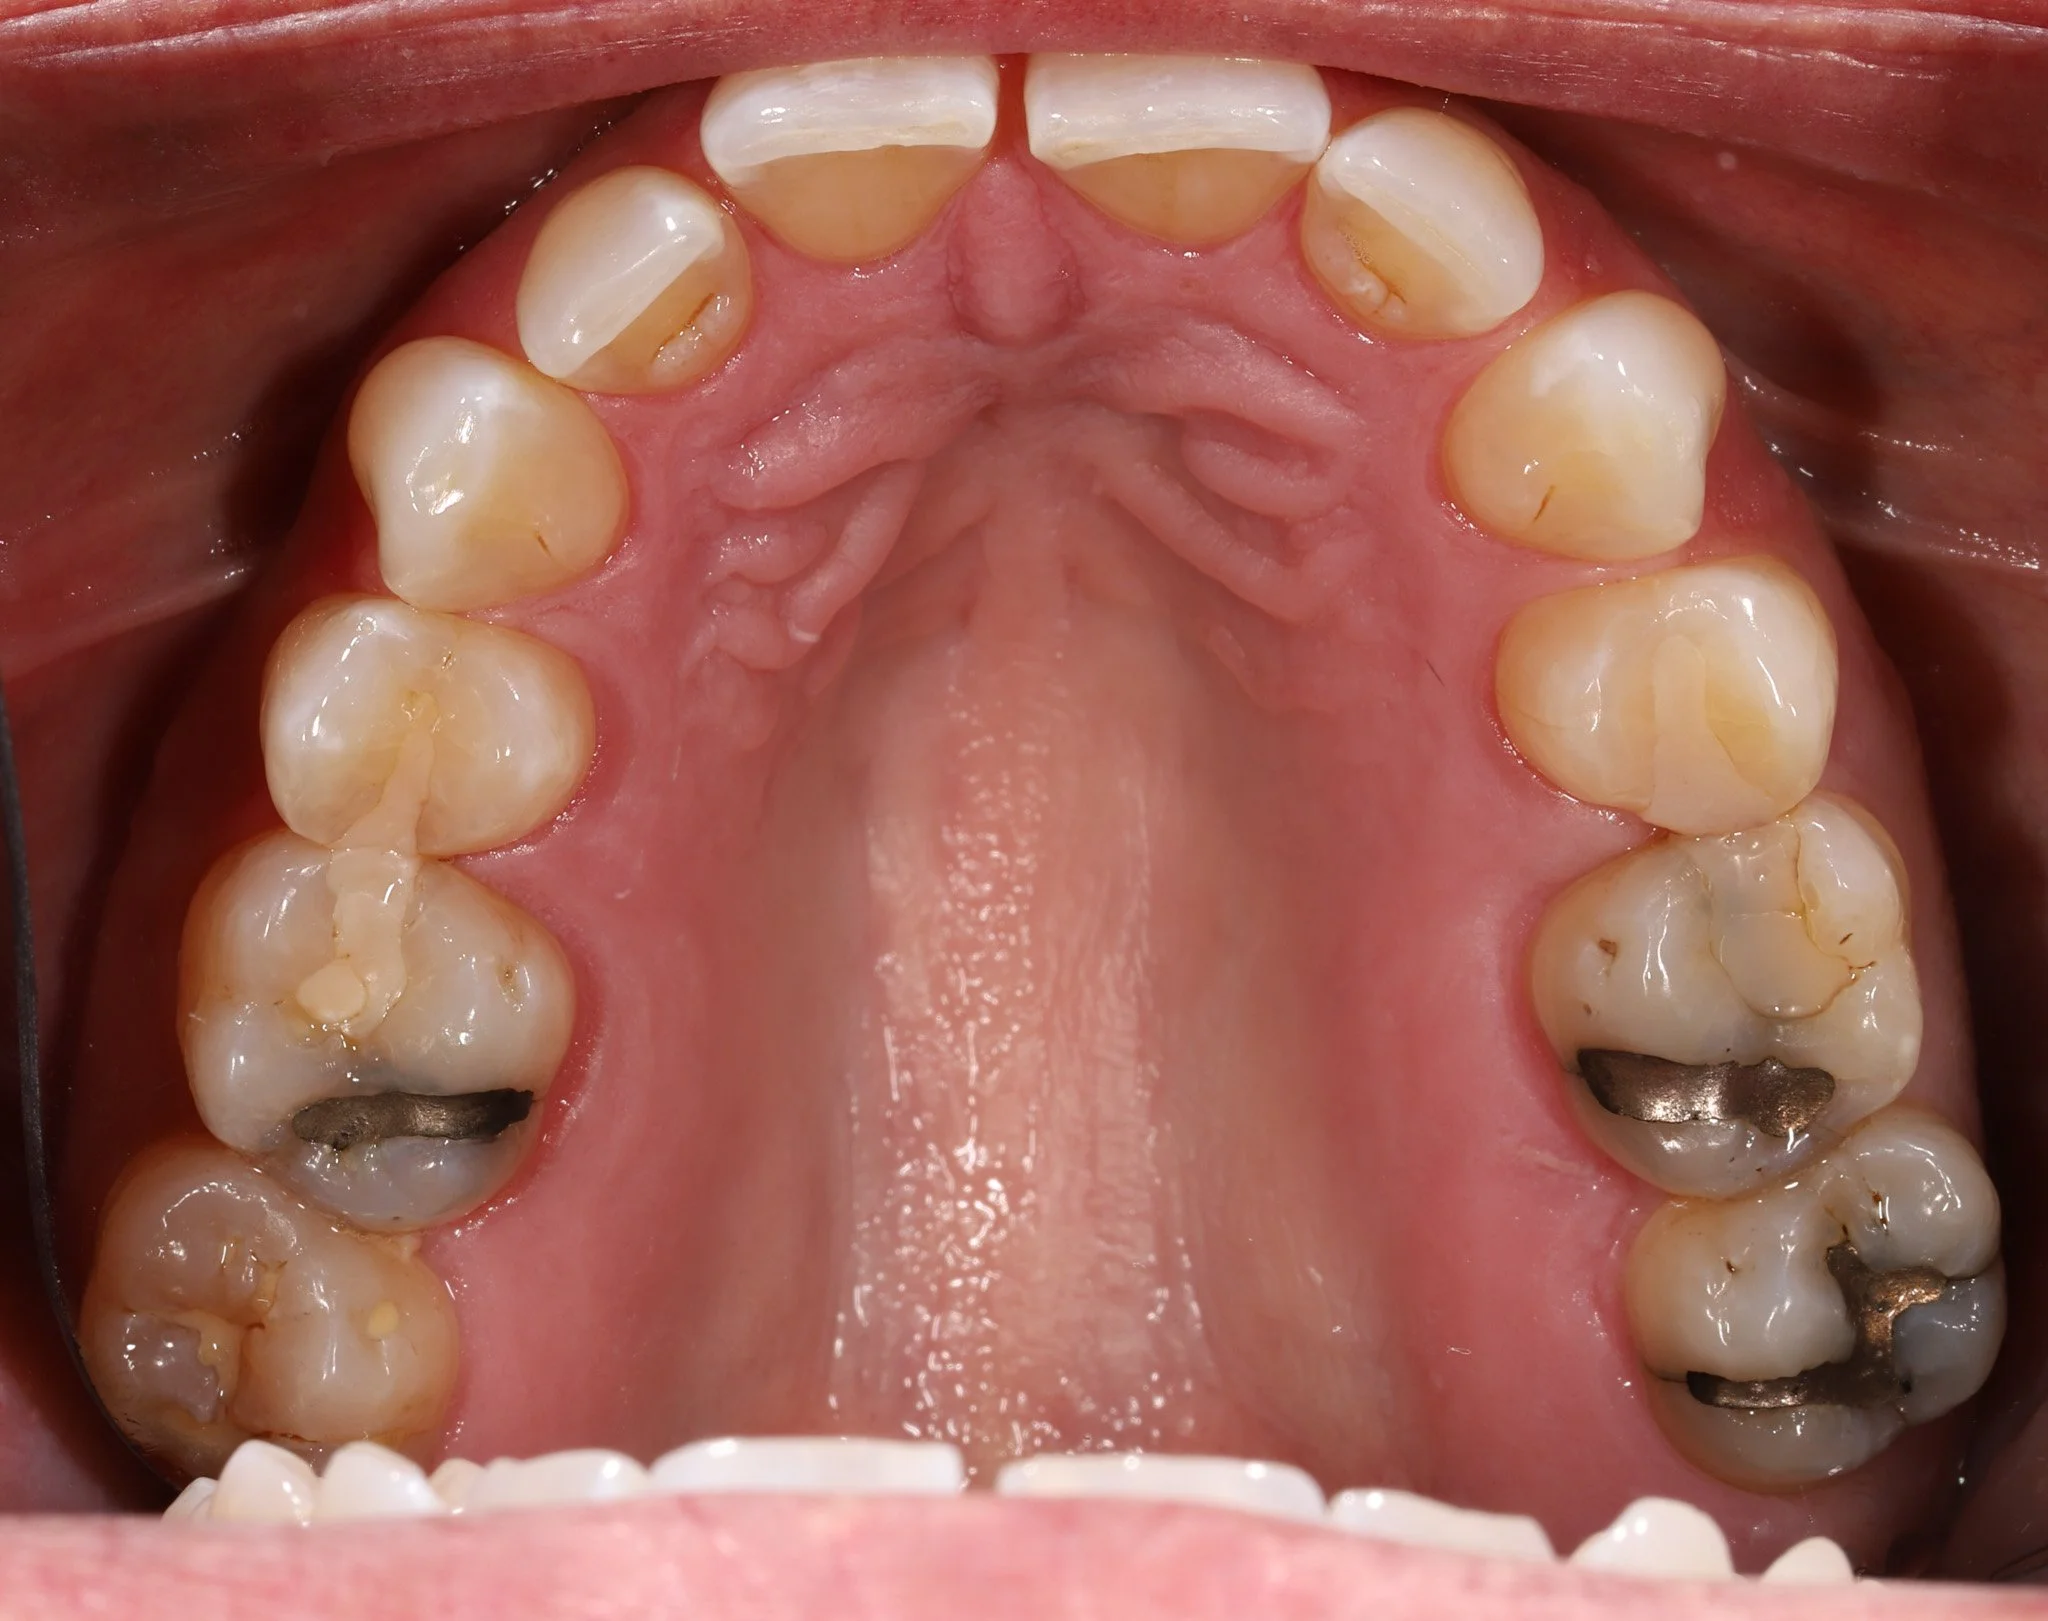

Close-up image of the upper molars in a person's mouth, with visible dental restorations, including a metal filling on the molar furthest back on the right and signs of dental wear or decay on the other teeth.

Before: Cracked teeth, leaking fillings, decay